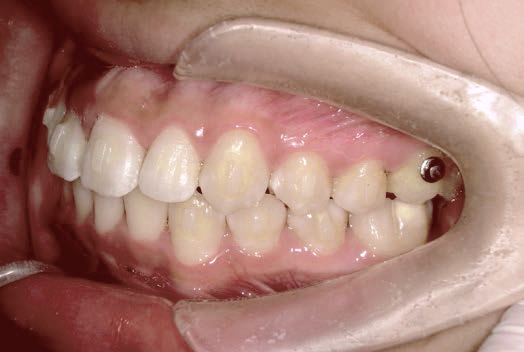

出っ歯

あごや骨格を正しく成長させる矯正治療

Aさん (矯正開始時:8歳)

Before

After

鼻がつまりやすく、口呼吸をしているために上あごが狭い状態でした。また上の前歯がかなり前へ傾いているため、お口をきちんと閉じていることができません。さらに、下の前歯もでこぼこしていました。

治療を終えて

装置によって上あごを拡大し、下あごを少し前へ成長させたことで、永久歯がきれいに並ぶスペースを確保しました。また、お口の機能が向上したことから鼻がよく通るようになり、口呼吸も改善され口も閉じやすくなったので顔の表情もよくなりました。

主訴・治療内容 下あごが後ろに下がり、出っ歯のようになっていることを心配して、無料相談に来院されました。

治療期間 2年半

費用 462,000円(税込)